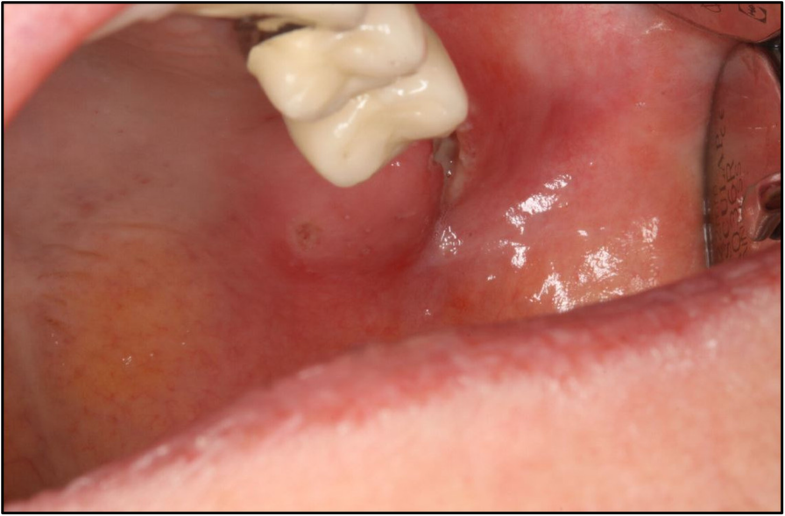

Lymph node abscess caused by Francisella tularensis a rare Abscess Lymph Node lymphadenitis is infection of one or more lymph nodes, which usually become swollen and tender. if infection is the cause of your swollen lymph nodes and isn't treated, an abscess may form. lymph nodes may feel rubbery if an abscess (pocket of pus) has formed or they have become inflamed. Nodes that increase in size. enlarged. Abscess Lymph Node.

Lymph node abscess caused by Francisella tularensis a rare Abscess Lymph Node Symptoms include pain, tenderness, and lymph node enlargement. Nodes that increase in size. lymphadenitis is an acute infection of one or more lymph nodes. if infection is the cause of your swollen lymph nodes and isn't treated, an abscess may form. lymphadenitis is infection of one or more lymph nodes, which usually become swollen and tender. . Abscess Lymph Node.

(PDF) Lymph node abscess caused by Francisella tularensis a rare Abscess Lymph Node symptoms caused by an infected lymph node or group of nodes may include: lymph nodes may feel rubbery if an abscess (pocket of pus) has formed or they have become inflamed. Nodes that increase in size. lymphadenitis is infection of one or more lymph nodes, which usually become swollen and tender. lymphadenitis is an acute infection. Abscess Lymph Node.